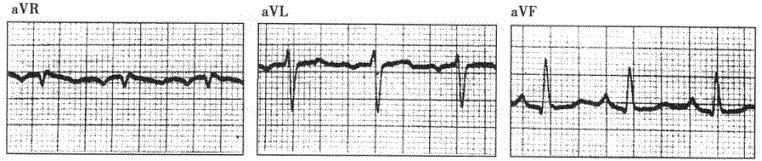

患者女性,76岁,慢性咳喘33年,临床诊断慢性肺源性心脏病。心电图检查如下图所示。???心电图最可能的诊断为A.左心室肥大B.左后分支...